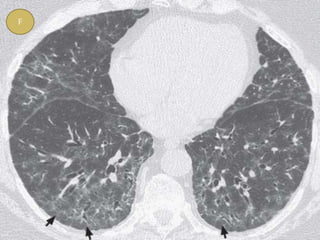

 Typical HRCT findings- GGO , irregular linear

opacity ( reticulations ), traction bronchietasis.

F

 Characteristic finding of NSIP is relative

sparing of the immediate subpleural lung in

dorsal region of lower lobe.